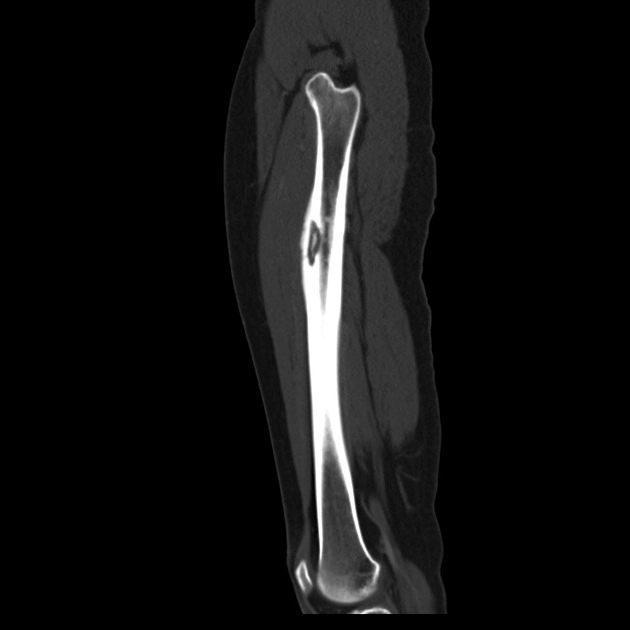

Mảnh xương chết (Sequestrum)

16/03/2026